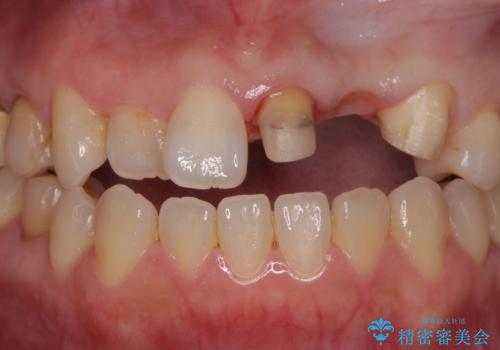

- 前歯がクラグラして噛めないことの改善を求めて来院されました。

X線撮影や歯周組織検査から、クラウン下の虫歯の再発や歯の破折が疑われる状況でした。

左上2は、クラウン メタルコアの除去を行ったところ虫歯の再発や亀裂を認め、長期的な予後の期待が難しいことから抜歯を行い

ブリッジで審美性の回復を行っていく運びとなりました。